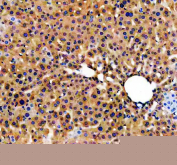

IHC staining of FFPE human liver tissue with Apolipoprotein H antibody, HRP-secondary and DAB substrate. HIER: boil tissue sections in pH8 EDTA for 20 min and allow to cool before testing.

IHC staining of FFPE human liver cancer tissue with Apolipoprotein H antibody, HRP-secondary and DAB substrate. HIER: boil tissue sections in pH8 EDTA for 20 min and allow to cool before testing.

IHC staining of FFPE mouse liver tissue with Apolipoprotein H antibody, HRP-secondary and DAB substrate. HIER: boil tissue sections in pH8 EDTA for 20 min and allow to cool before testing.